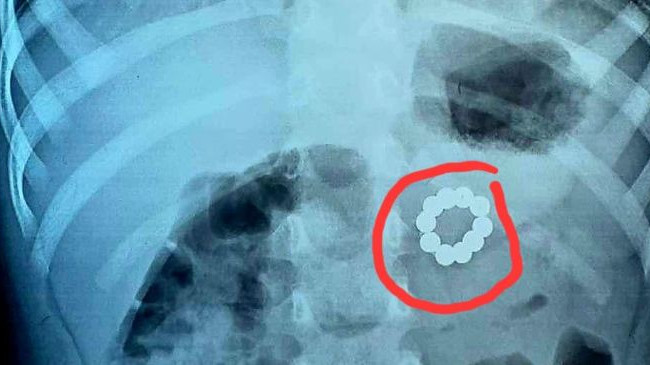

Медики Ивано-Франковской областной детской клинической больницы из желудочно-кишечного тракта трехлетней девочки удалили 21 неодимовый магнит. Об этом сообщил Департамент здравоохранения Ивано-Франковской ОГА.

В медучреждение обратилась мать маленькой пациентки с жалобами у дочери на кашель и боль в животе. При обследовании на догоспитальном этапе в желудочно-кишечном тракте маленькой пациентки были обнаружены неодимовые магниты.

«Удаление эндоскопически было невозможно, поэтому провели оперативное вмешательство, во время которого удалили 10 магнитов из толщи задней стенки желудка и еще 11 из начального отдела подвздошной кишки. Из дополнительного анамнеза установлено, что они находились в ЖКТ ребенка больше месяца!», - говорят медики.